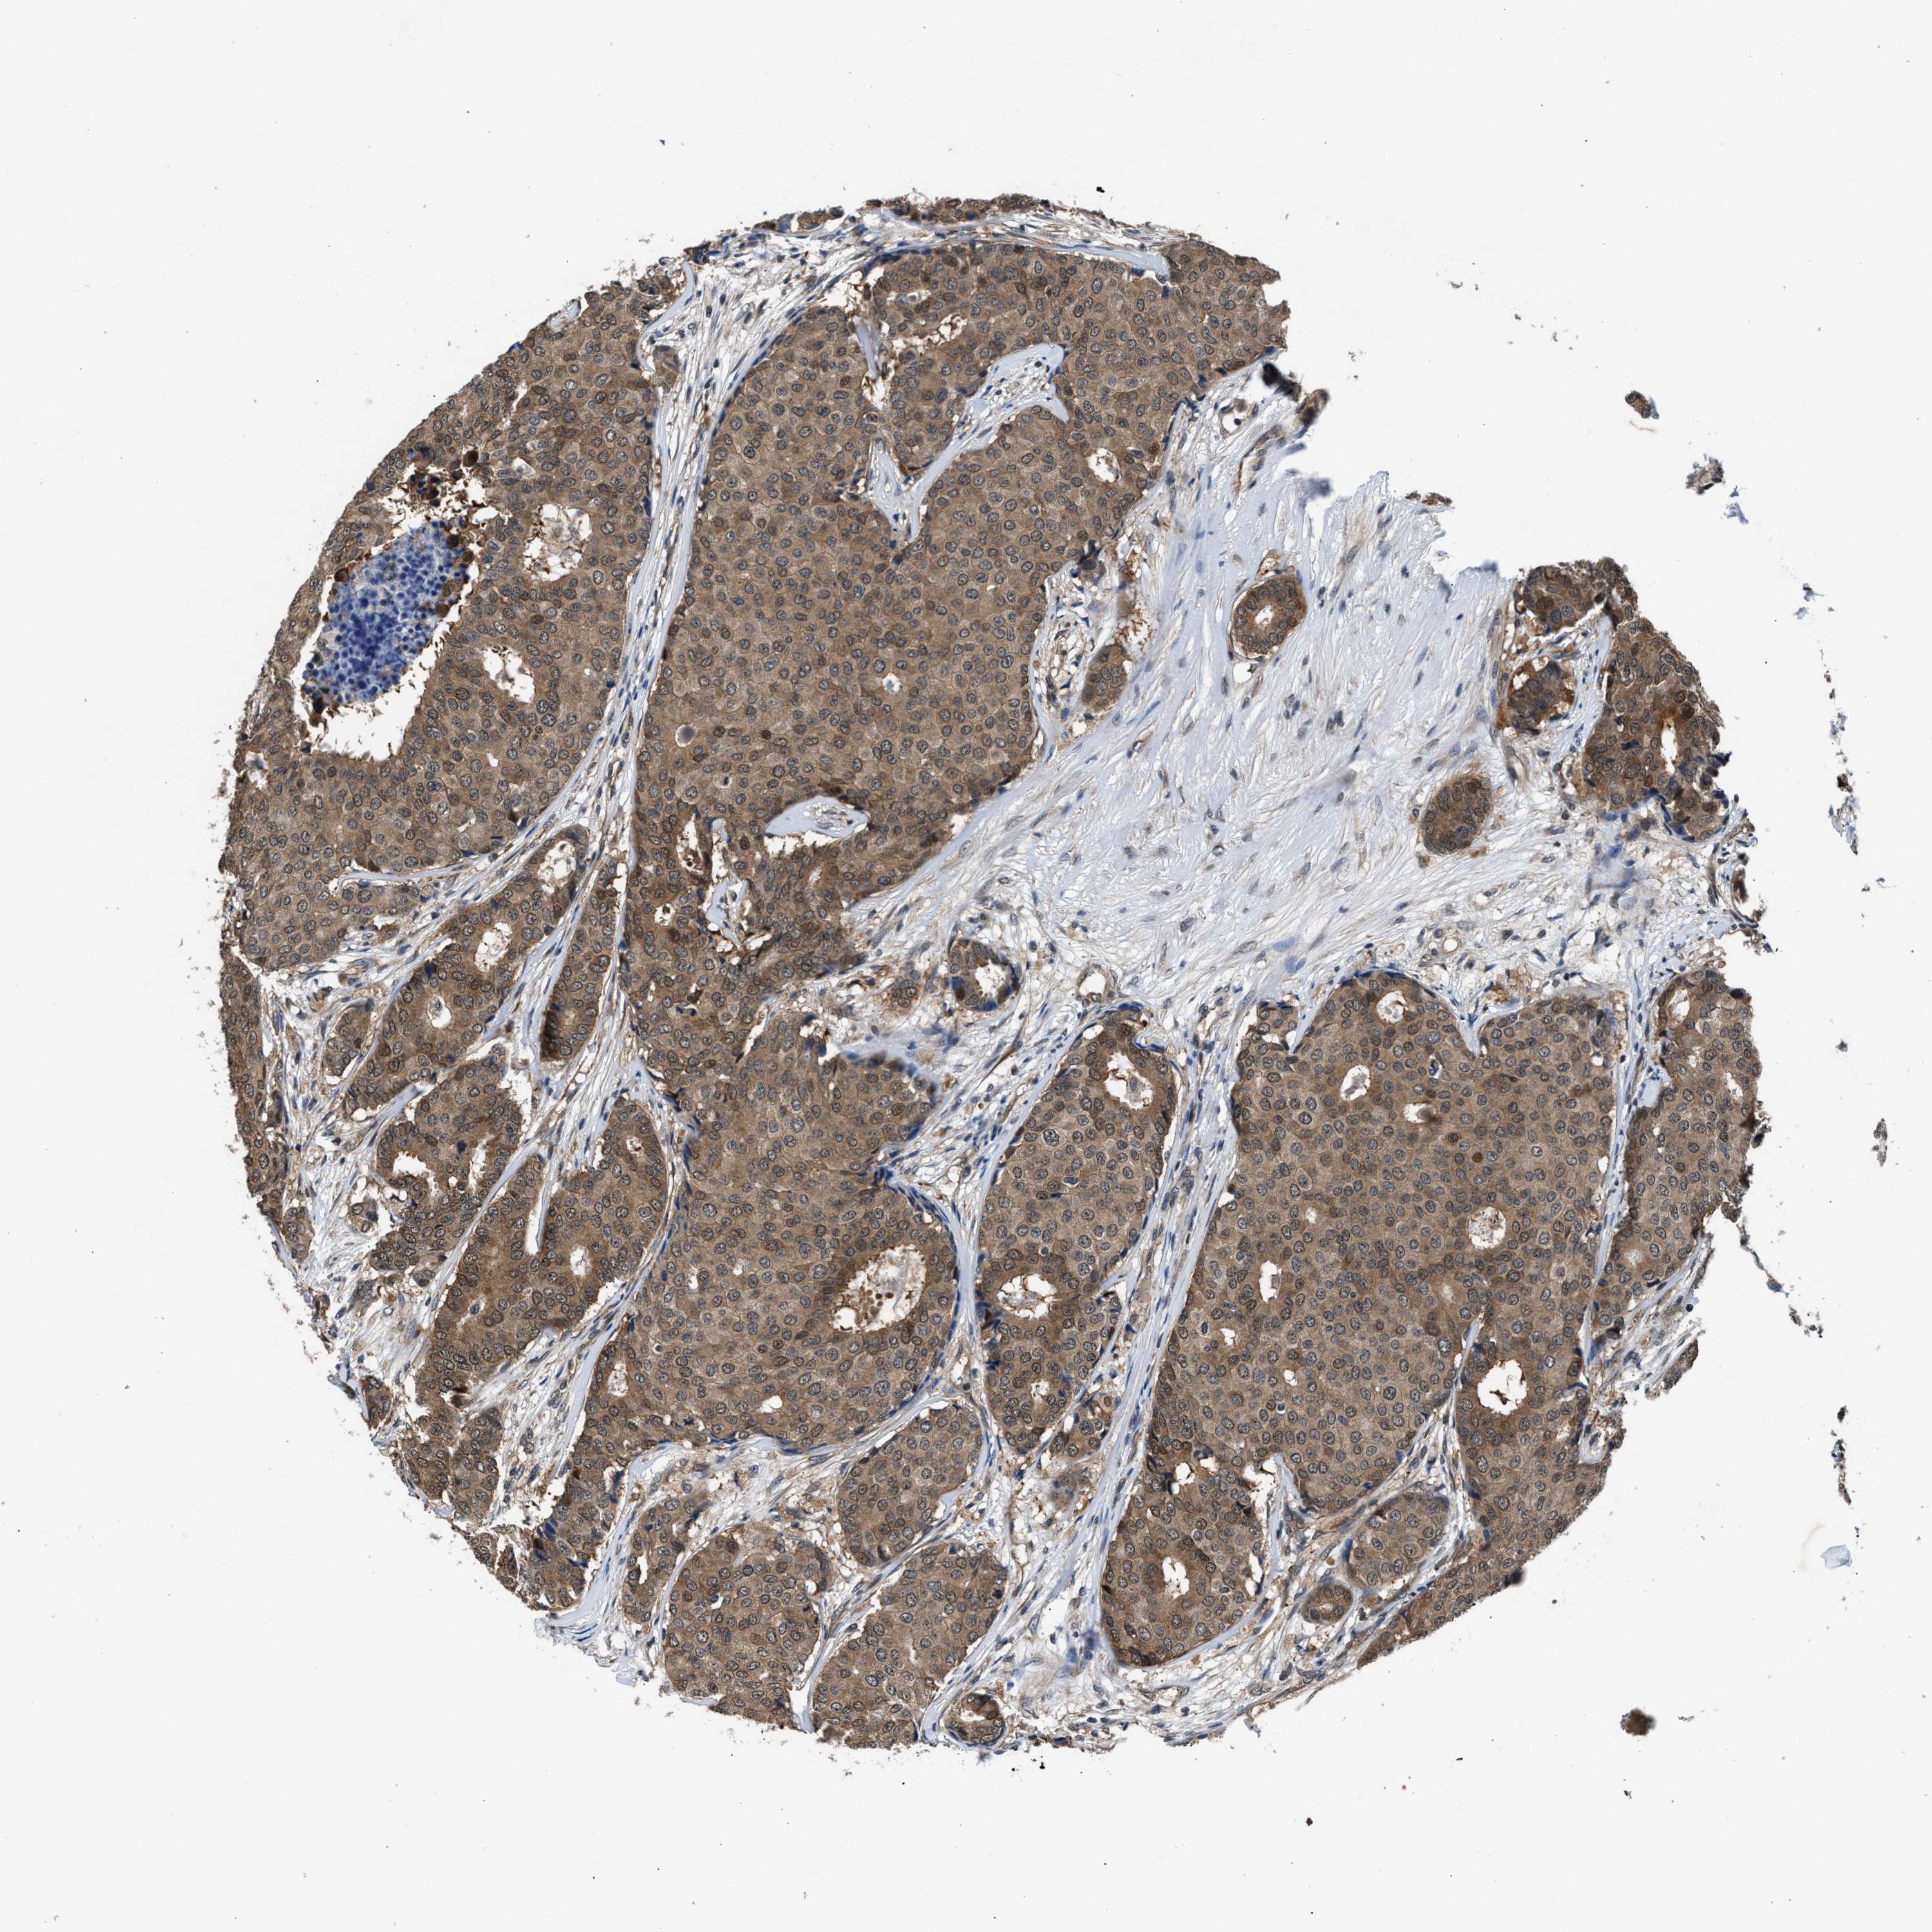

CANCER BREAST CANCER Show tissue menu

BRCA TCGA BRCA VALIDATION PROTEIN EXPRESSION